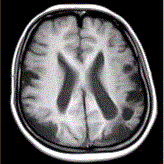

问题 女性,22岁。癫痫发作及智力异常。MRI显示见下图。 该病的诊断为

选项 A.海绵状血管瘤 B.发育性静脉畸形 C.AVM D.毛细血管扩张症 E.动脉瘤 F.硬脑膜动静脉漏 G.moyamoya

答案 G